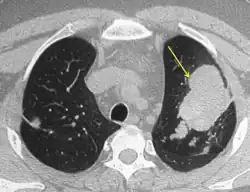

CT of the chest showing high attenuation mucous (HAM) impaction (yellow arrow). This is considered pathognomic for allergic bronchopulmonary aspergillosis (ABPA).